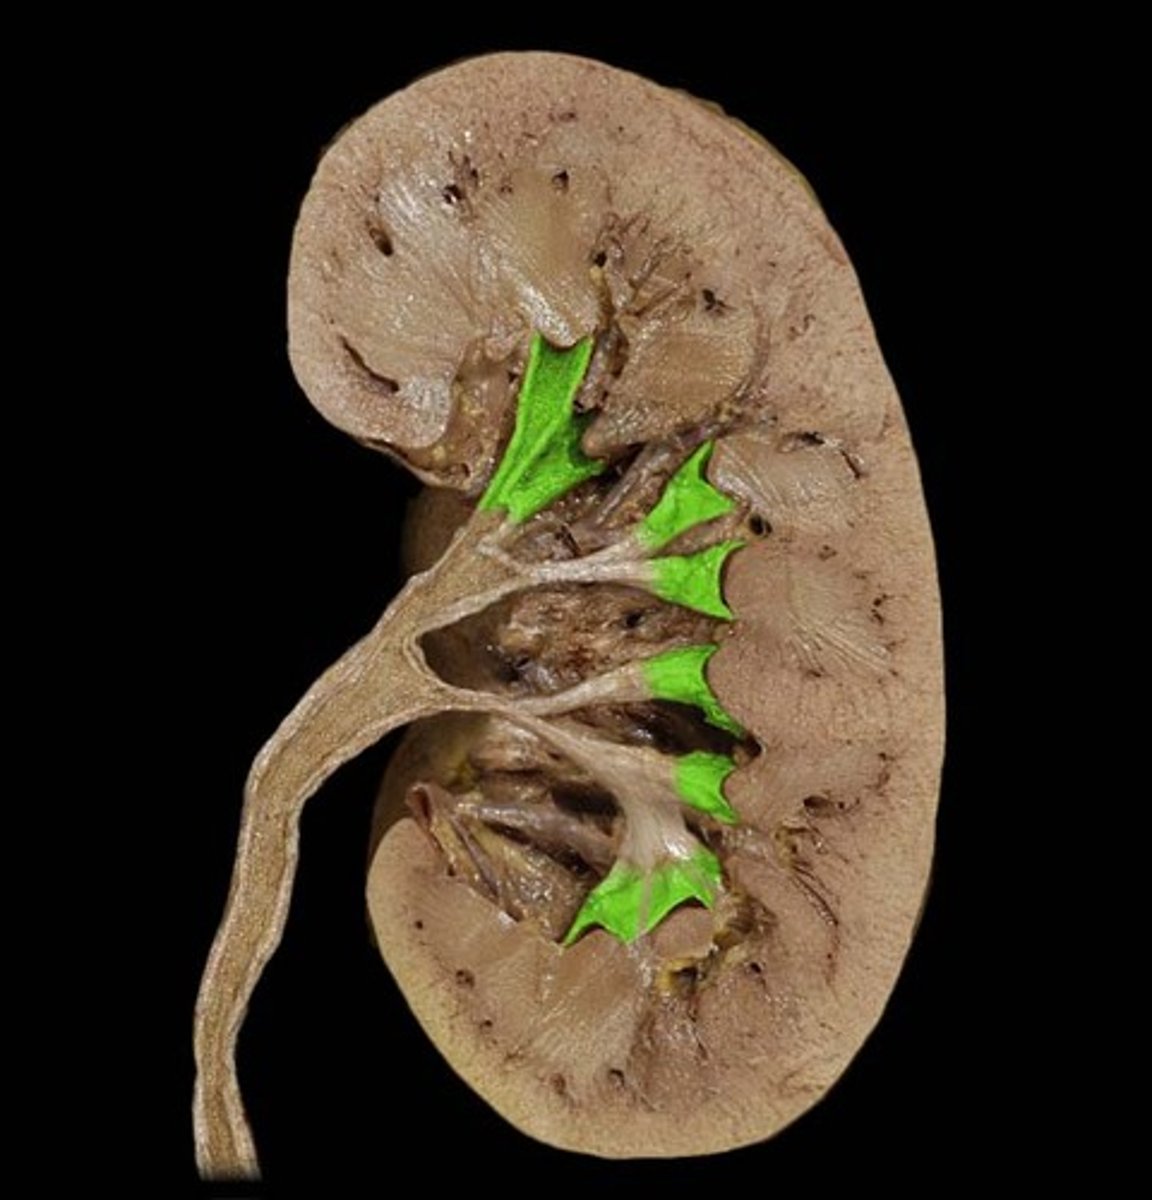

minor calyx

cup that nestles the papilla of each pyramid; collects its urine

major calyx

urine passageway

renal pelvis

central collecting region in the kidney